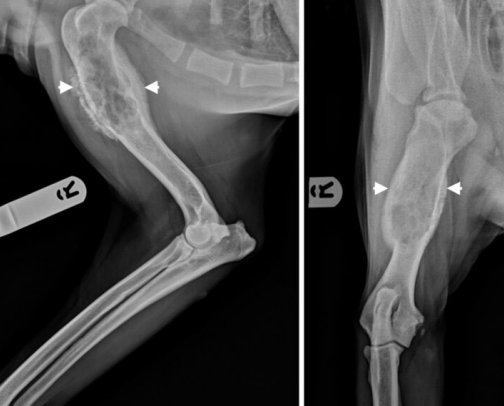

- Osteosarcoma (๊ณจ์ก์ข

) : ๊ฐ์์ ๊ฐ์ฅ ํํ malignant bone tumor.

- ๊ธด๋ผ์ metaphysis ๋ถ์, ๋ํ๊ฒฌ์์ ์ ๋ฐ์ํจ.

Diagnosis

- ๋ํ๊ฒฌ์์ ๋ฐ์ ํ๋ฅ ๋์. ์ํ๊ฒฌ์์๋ ๋ชธํต ๊ณจ๊ฒฉ์ ๋ ์ ๋ฐ์.

- lameness, localized limb swelling, pain, reluctance to walk